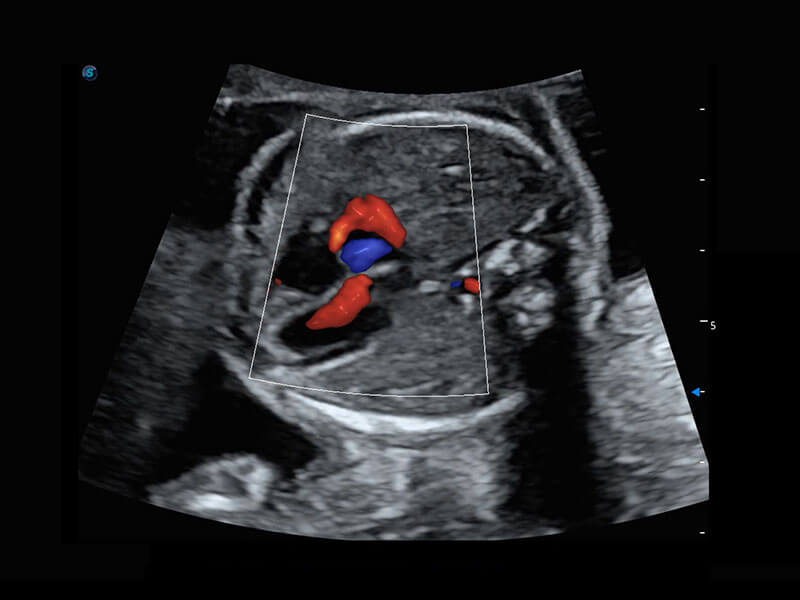

P60搭载一系列胎儿心脏成像技术,实现精细的胎儿心脏评估。

四腔心血流